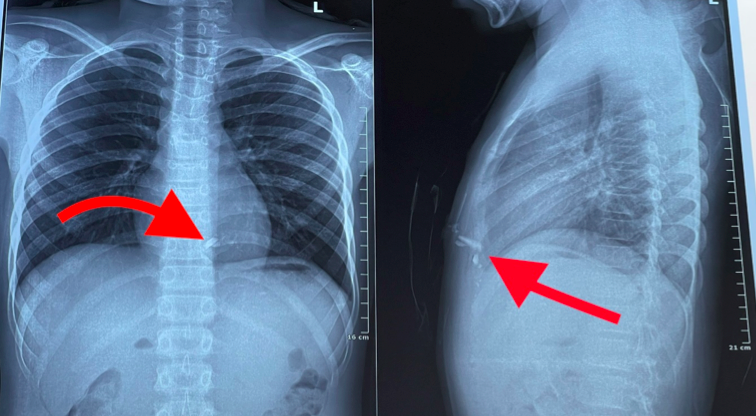

Chụp phim X-quang ngực thấy có 2 dị vật kim loại trong lồng ngực nằm sau xương ức bên trái, nghi ngờ tổn thương tim. Các bác sĩ đã nhanh chóng mổ cấp cứu kịp thời lấy dị vật, khâu vết thương thành thất phải cho bệnh nhân.